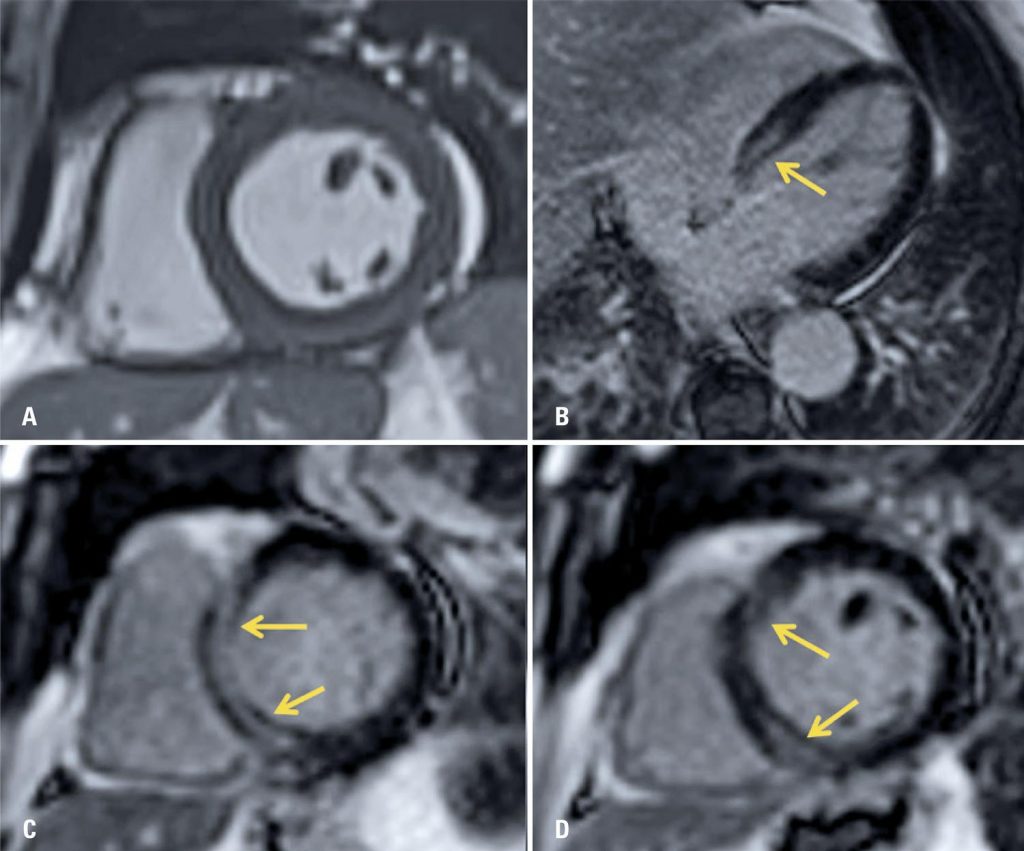

Figure 3

Cardiac magnet resonance imaging images on short axis. (A) and late myocardial enhancement sequences on the long axis of the four chambers (B) and short axis; (C and D) showing areas of late enhancement with non-ischemic pattern on the septal base wall of the left ventricle (arrows), findings that, in the clinical scenario, suggest inflammatory/infectious process (myocarditis)